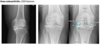

**Colles - ‘dinner fork type deformity’** Features of the injury 1. Transverse fracture of the radius 2. 1 inch proximal to the radio-carpal joint 3. Dorsal displacement and angulation of the distal radius

Colles fracture ## Footnote Typically FOOSH forwards Extra-articular radial # with dorsal (posterior / back of hand) angulation and displacement